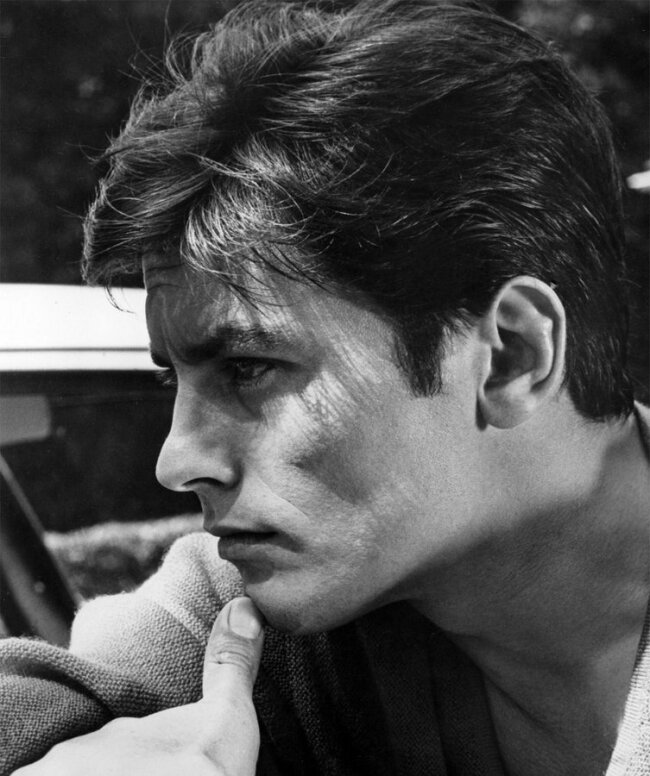

Case study #2)

A good way to check this is to see caucasoids who are class 3 - this eliminates and controls for the Asian trait of having an entirely recessed midface.

In the before the ANS is clearly further projected than the A point as can be seen by the curve. My logic follows that the nose is relatively projected which follows the norm of caucasoids but due to class 3 it is evident that the A point will be further back relative to the ANS. Now when he advanced the A point during the lefort 1 he fixed his profile - it looks nice and way better than the before but now the nasolabial curve has gone (not that it was good before but this is just theory talk).

Case study #2)

A good way to check this is to see caucasoids who are class 3 - this eliminates and controls for the Asian trait of having an entirely recessed midface.

In the before the ANS is clearly further projected than the A point as can be seen by the curve. My logic follows that the nose is relatively projected which follows the norm of caucasoids but due to class 3 it is evident that the A point will be further back relative to the ANS. Now when he advanced the A point during the lefort 1 he fixed his profile - it looks nice and way better than the before but now the nasolabial curve has gone (not that it was good before but this is just theory talk).